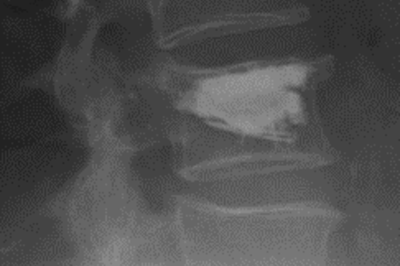

• Wirbelbruch mit Spinalkanalstenose

Röntgenbild Wirbelbruch mit Spinalkanalstenose

Traumatische, komplette Berstungsfraktur mit hochgradiger Spinalkanalstenose